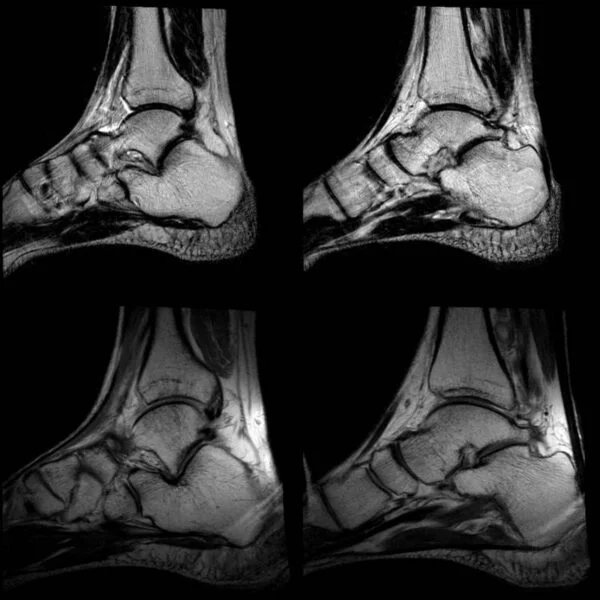

ToggleSkręcenie stawu skokowego

Staw górny i dolny łączą kośc piszczelową, kość strzałkową a także kość skokową i piętową.

Jak istotna dla całego organizmu może być kontuzja kostki możemy przeanalizować zastanawiając się, które struktury podczas skręcenia bocznego będą poszkodowane najczęściej i jaką drogą mogą powstawać: